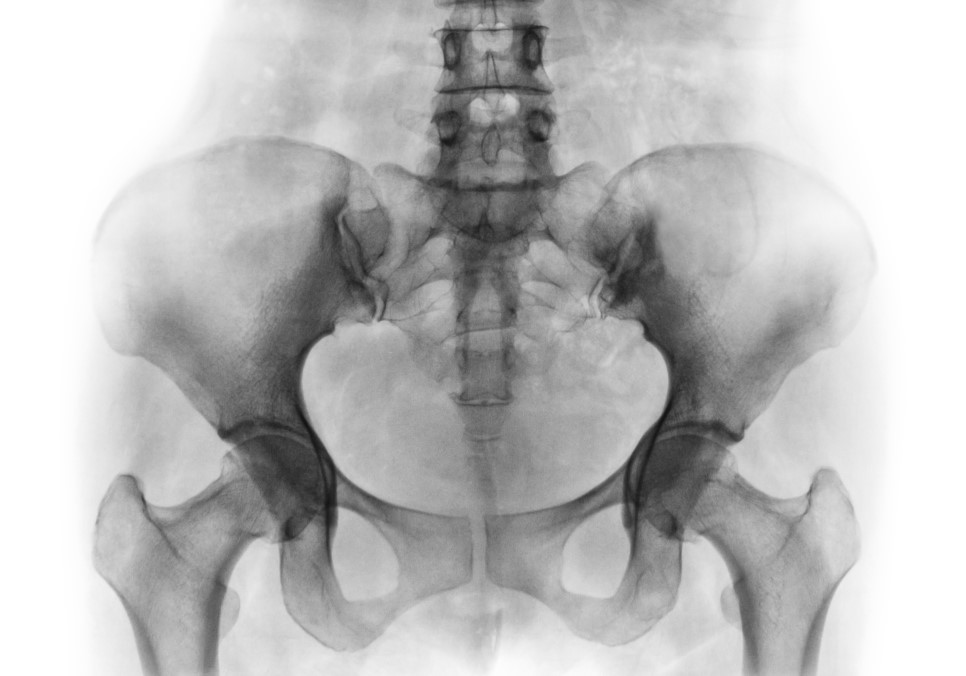

다리와 척추를 이어주는 우리 몸의 중심, 골반입니다. 윗부분은 넓고 아랫부분은 좁은 원뿔 모양의 골반은 소화기와 생식기를 감싸 이를 보호하고 떠받쳐서 아래로 쳐지는 것을 방지하는 역할도 합니다. 골반이 틀어지면 신체 균형이 무너지고 척추 정렬에도 문제가 생깁니다. 하체비만, 보행 시 자세 변화, 척추측만증, 허리디스크 등으로 이어질 수 있어 주의가 필요합니다.